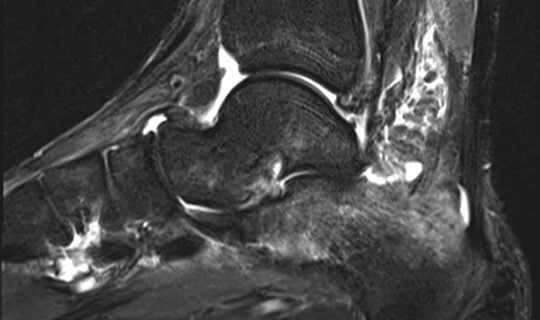

Ankle MRI : A Systematic Approach